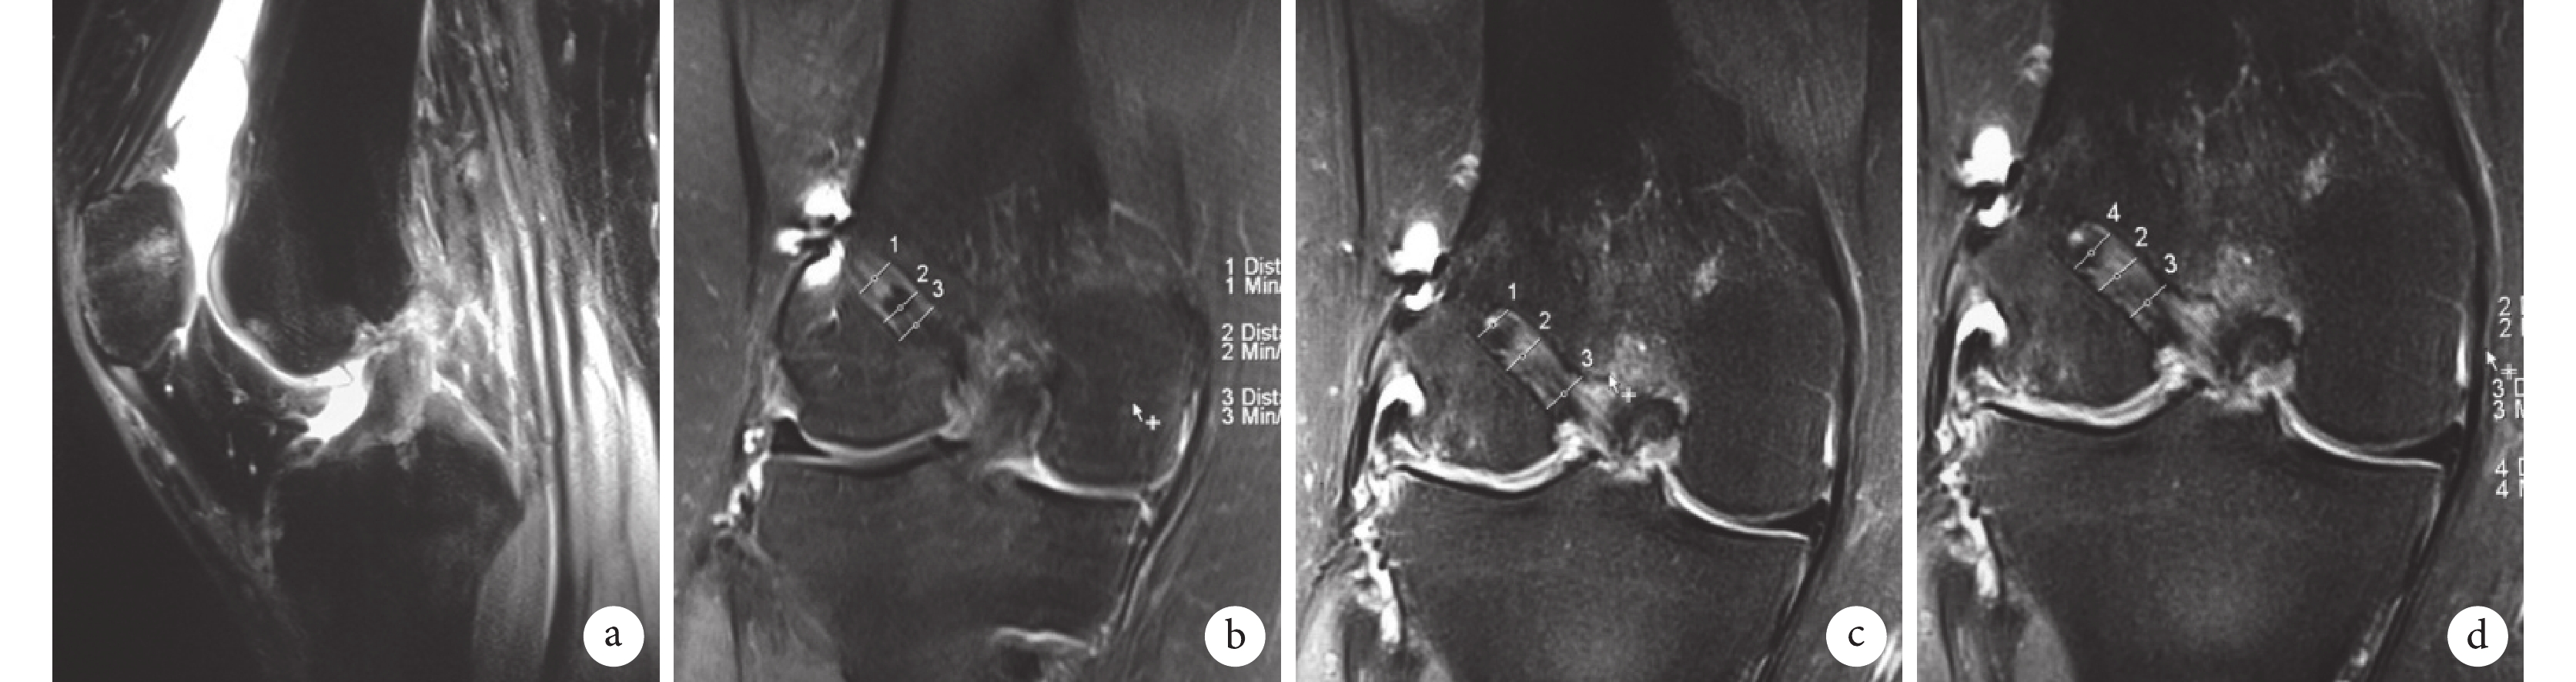

兩組患者術后均獲隨訪 48 周。術后切口均Ⅰ期愈合,無 1 例出現關節內感染及關節粘連等并發癥。術后兩組患者前抽屜試驗、Lachman 試驗及軸移試驗均為陰性。術后 6、24、48 周,試驗組 Lysholm 評分均明顯高于對照組,比較差異有統計學意義(P<0.05);但兩組間膝關節活動度比較差異無統計學意義(P>0.05)。術后 6 周,兩組 HSS 評分比較差異無統計學意義(P>0.05);24、48 周試驗組評分明顯高于對照組,比較差異有統計學意義(P<0.05)。見表 1~3。MRI 復查示,術后 6 周試驗組移植物新生血管活躍,含水量較高,再血管化進程較對照組快,移植物信號高于對照組;24、48 周,試驗組移植物信號已向正常韌帶低信號轉變,移植物信號較對照組低,移植物血管化及韌帶化進程較對照組快。見圖 3、4。術后 6、24、48 周兩組移植物信號強度、骨隧道擴大程度、移植物信噪比比較,差異均有統計學意義(P<0.05)。術后 6、24 周兩組移植物腱-骨結點 T2 值比較,差異有統計學意義(P<0.05);48 周比較差異無統計學意義(P>0.05)。見表 4。

a. 術前;b. 術后 6 周;c. 術后 24 周;d. 術后 48 周

Figure3. MRI of a 32-year-old male patient with right ACL injury in the trial groupa. Before operation; b. At 6 weeks after operation; c. At 24 weeks after operation; d. At 48 weeks after operation